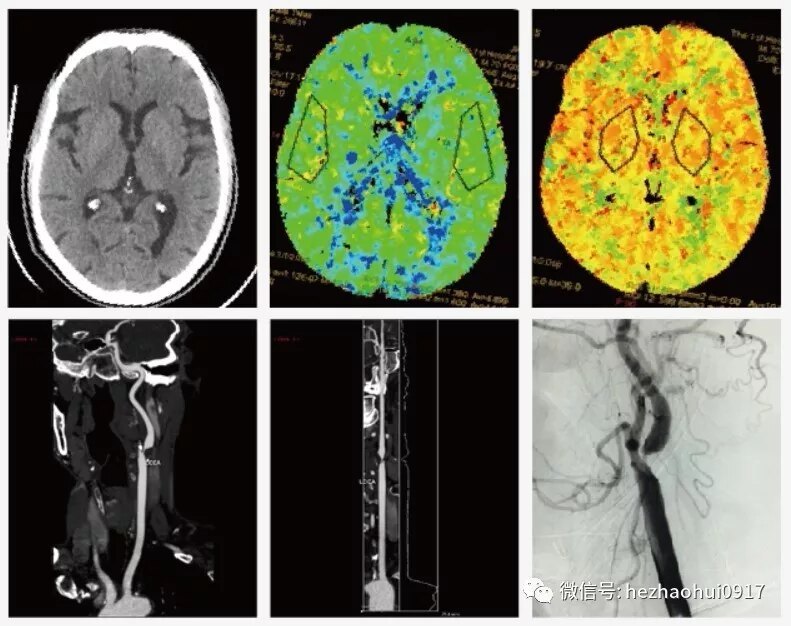

病史簡介: 70歲男患,因“發(fā)作性吐詞不清、右上肢無力2+月”入院。2+月前曾就診于某區(qū)人民醫(yī)院,全腦血管造影示左側(cè)頸內(nèi)動脈起始段粥樣斑塊形成伴重度狹窄。 既往史及家族史:吸煙史50年。 輔助檢查: 術(shù)前CT、CTP、CTA及外院DSA: 診斷: 1.左側(cè)頸內(nèi)動脈重度狹窄 2.左側(cè)鎖骨下動脈起始端閉塞 3.短暫性腦缺血發(fā)作 手術(shù):左側(cè)頸動脈內(nèi)膜剝脫術(shù) 術(shù)后檢查: 術(shù)后CT、CTP及CTA: 術(shù)后情況: 患者恢復(fù)良好,吐字清晰,右上肢自覺力量恢復(fù)良好。 導(dǎo)語 調(diào)查研究發(fā)現(xiàn),隨著人民生活水平的提高,腦血管疾病的發(fā)病率逐年上升,腦卒中已成為中國居民死亡排名首位的原因,而在腦卒中患者中,缺血性卒中占80%左右,其中 25%~30%的缺血性腦卒中與頸動脈狹窄密切相關(guān),嚴(yán)重的腦梗塞可導(dǎo)致患者殘疾甚至死亡,頸動脈狹窄儼然已經(jīng)成為當(dāng)今社會危害人民健康的“頭號殺手”之一。 什么是勁動脈狹窄? 人過中年以后血脂容易增高,導(dǎo)致血粘稠度增高,血流速度減慢;血脂沉積在血管內(nèi)膜導(dǎo)致頸動脈內(nèi)膜增厚,嚴(yán)重者可以在局部形成斑塊導(dǎo)致頸動脈狹窄。一方面斑塊可以阻塞血管,導(dǎo)致腦供血不足;另一方面斑塊可能脫落導(dǎo)致腦梗塞,嚴(yán)重腦梗塞可導(dǎo)致患者殘疾甚至死亡。 手術(shù)方式選擇 目前治療頸動脈狹窄的主要手術(shù)方式為頸動脈內(nèi)膜剝脫術(shù)(CEA)和頸動脈支架置入成形術(shù)(CAS)。CEA可以徹底清除動脈硬化斑塊、重建正常血管和血流,治療效果可靠,同時(shí)復(fù)發(fā)率低,手術(shù)費(fèi)用低,50年來一直是國際公認(rèn)的手術(shù)治療頸動脈狹窄的“金標(biāo)準(zhǔn)”。 CAS采用球囊或是支架擴(kuò)張頸動脈的狹窄部位,從而達(dá)到重建頸動脈血流的目的。操作相對簡單,創(chuàng)傷小,恢復(fù)快;但創(chuàng)傷小并不意味著風(fēng)險(xiǎn)小,而且,因?yàn)椴荒軓氐浊宄邏K,只是把斑塊推擠到血管邊壁上,所以復(fù)發(fā)率高,另外費(fèi)用也相對較高。 事實(shí)上,兩種治療方法都有其科學(xué)性和合理性,各有優(yōu)缺點(diǎn),不必過分追究具體哪種手術(shù)方式孰優(yōu)孰劣。臨床工作中應(yīng)全面綜合考慮各方面因素,選擇最適合患者的個(gè)體化治療方式。 目前,國內(nèi)更多的患者偏向于選擇CAS,而CEA卻尚未廣泛開展,原因有很多:頸動脈狹窄患者很多都收入到內(nèi)科病房,內(nèi)科醫(yī)生通常只會做CAS,不會做CEA,沒有向患者說明有兩種手術(shù)方式,或者說明了兩種手術(shù)方式,但過度強(qiáng)調(diào)了CEA的風(fēng)險(xiǎn),而淡化了CAS的風(fēng)險(xiǎn);其次,外科醫(yī)生對CEA宣傳力度也不夠;其他社會因素等。 我院是國家腦卒中篩查與防治工程委員會基地醫(yī)院,也是全國高級卒中中心。我們正努力加大腦梗塞和頸動脈狹窄防治的科普宣傳,增強(qiáng)大家對相關(guān)知識的認(rèn)識,早期篩查,及時(shí)治療,以免在出現(xiàn)嚴(yán)重腦梗塞后喪失最佳治療時(shí)機(jī)。 何朝暉簡介 神經(jīng)外科學(xué)博士、留美博士后、教授、主任醫(yī)師、碩士研究生導(dǎo)師、中共黨員。 任職情況: 國家衛(wèi)生計(jì)生委出血性卒中外科專業(yè)委員會常務(wù)委員。 國家衛(wèi)生計(jì)生委腦卒中防治委員會中青年委員。 中華中青年神經(jīng)外科醫(yī)師交流協(xié)會副會長,重慶地區(qū)會長。 重慶市醫(yī)學(xué)會神經(jīng)外科專業(yè)委員會腦血管外科手術(shù)學(xué)組委員。 國家自然科學(xué)基金委評議人。 《Behavioural Neurology》、 《BioMed Research International》、《Brain Research》、《Current Drug Targets》、《Neural Regeneration Research》、《Neurological Research》、《Chinese Neurosurgical Journal》、《重慶醫(yī)科大學(xué)學(xué)報(bào)》、《現(xiàn)代醫(yī)藥衛(wèi)生》審稿專家。 臨床工作方向: 出血性或缺血性腦血管疾?。ㄈ顼B內(nèi)動脈瘤、腦血管畸形、高血壓性腦出血、腦動脈硬化、腦供血不足、腦缺血、腦梗塞、頸動脈斑塊伴狹窄、煙霧病等)、腦腫瘤、顱腦外傷等。 擅長手術(shù): 顱內(nèi)動脈瘤瘤頸夾閉術(shù)、腦血管畸形切除術(shù)、頸動脈內(nèi)膜剝脫術(shù)、顱內(nèi)外血管搭橋術(shù)、腦腫瘤切除術(shù)等。 主持課題: 國家級課題3項(xiàng),省部級課題2項(xiàng),廳局級課題1項(xiàng),校級課題1項(xiàng),課題總經(jīng)費(fèi)100余萬。 發(fā)表論文: 共60余篇。SCI論文10余篇,其中《Stroke》(影響因子6.468)論著1篇,《Experimental Neurology》(影響因子4.645)論著1篇,合計(jì)影響因子約30分。 參編教材:1部;參編專著:2部。 教學(xué): 培養(yǎng)研究生30余名。 聯(lián)系方式: 微信公眾號:何朝暉腦科 好大夫在線:hezhaohuicqmu